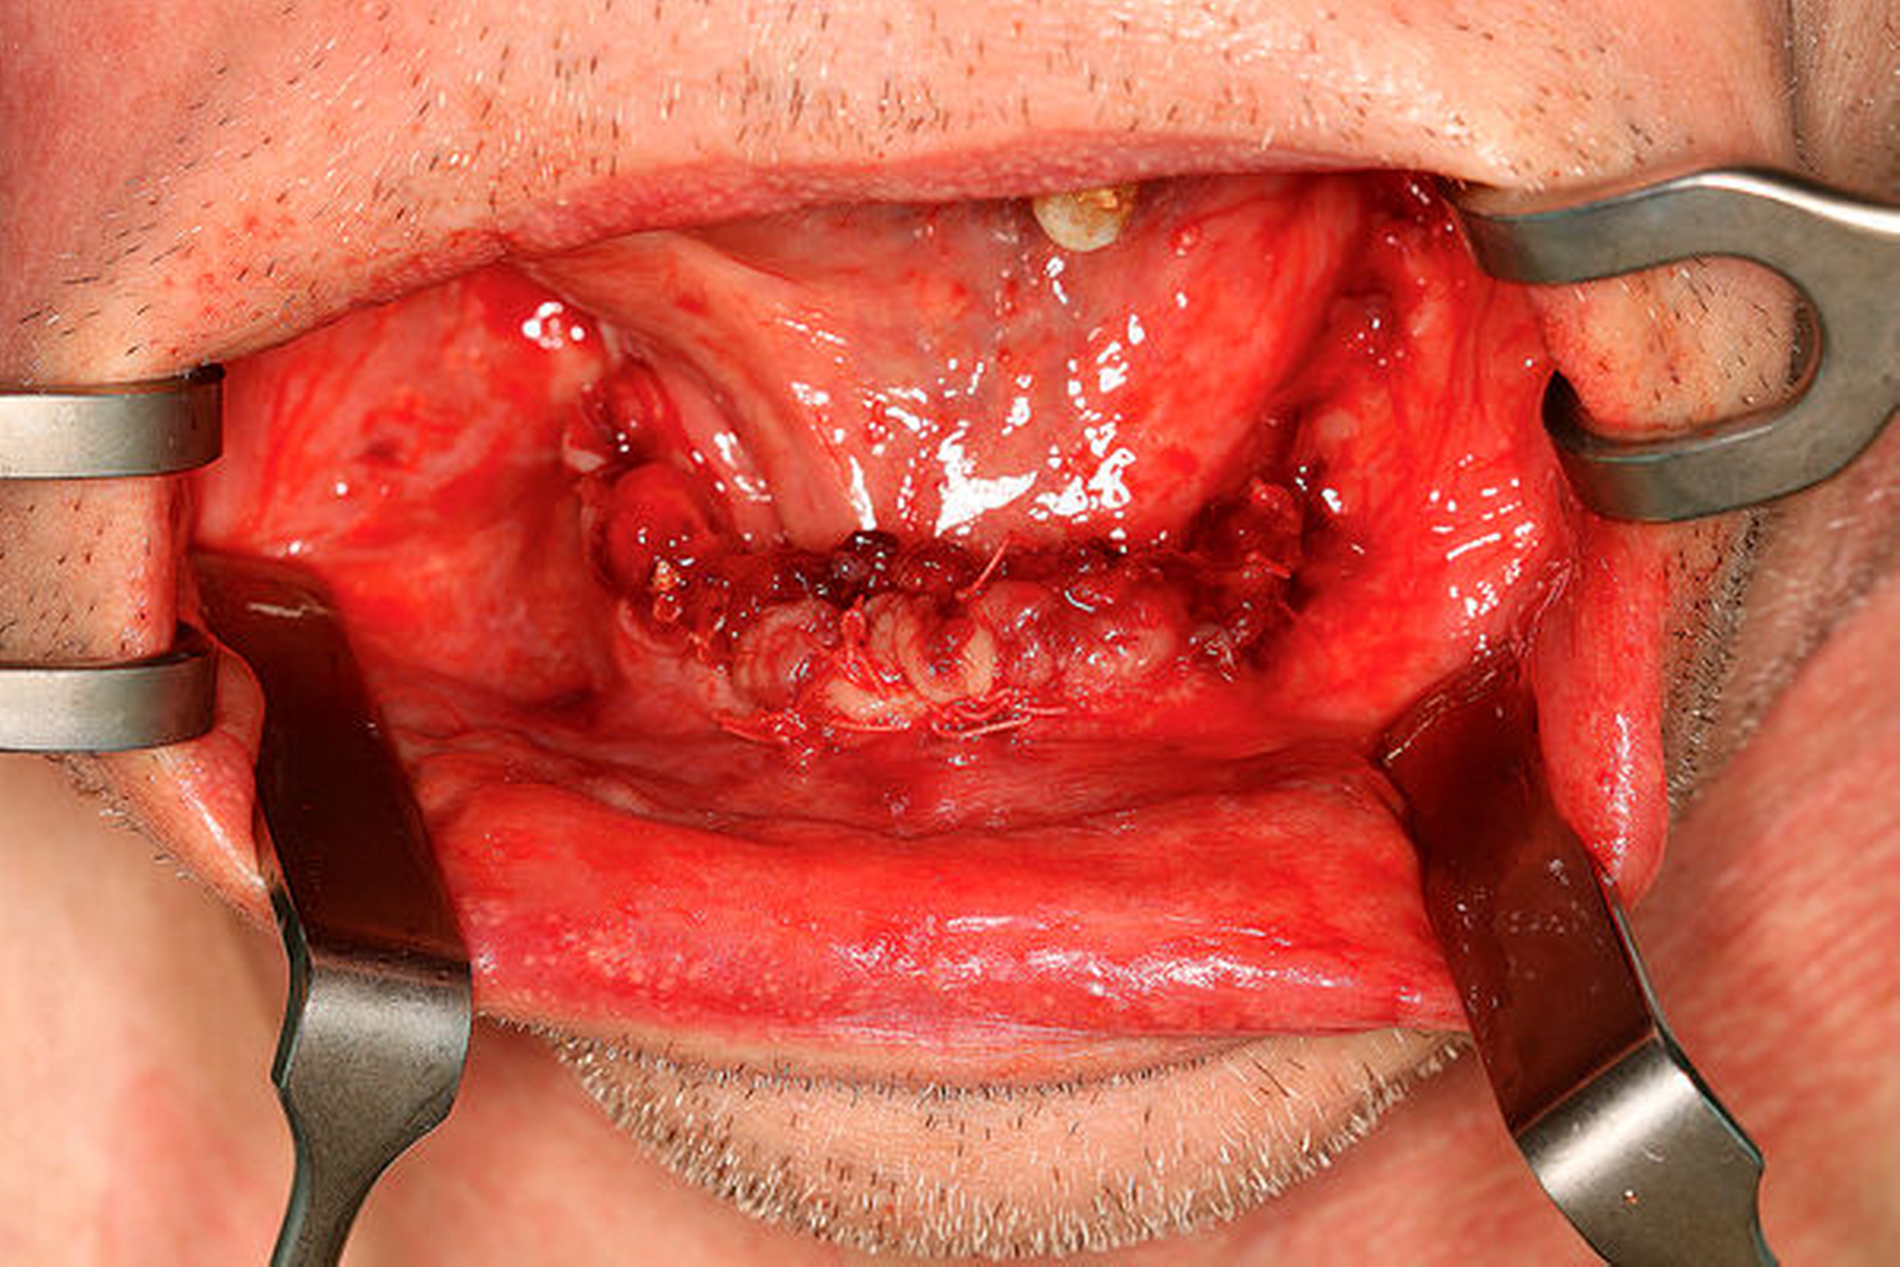

Am folgenden Tag sanierten wir den Patienten in Intubationsnarkose. Die Zahnsteinanteile wurden sukzessiv entfernt (Abbildung 7). Trotz des Versuchs, möglichst viele Zähne vom Zahnstein zu trennen und sie zu erhalten, zeigten sich insgesamt 19 Zähne als nicht mehr erhaltungswürdig (Abbildung 8). In vielen Fällen stellte sich nur noch marginaler oder gar kein Kontakt mehr zum Alveolarknochen dar. Lediglich im zweiten Quadranten konnten vier Zähne erhalten werden (23, 26, 27, 28) (Abbildung 9). Sämtliche Schleimhäute waren entzündlich verändert und zum Teil mit eitrigen und serösen Auflagerungen belegt (Abbildung 10). Zusätzlich wurde ein Abstrich des Ulkus von intraoral genommen. Hier zeigte sich nach Bebrütung ein Staphylokokkus capitis, welcher gegen die Reserveantibiotika Vancomycin, Teicoplanin und Fosfomycin resistent war.